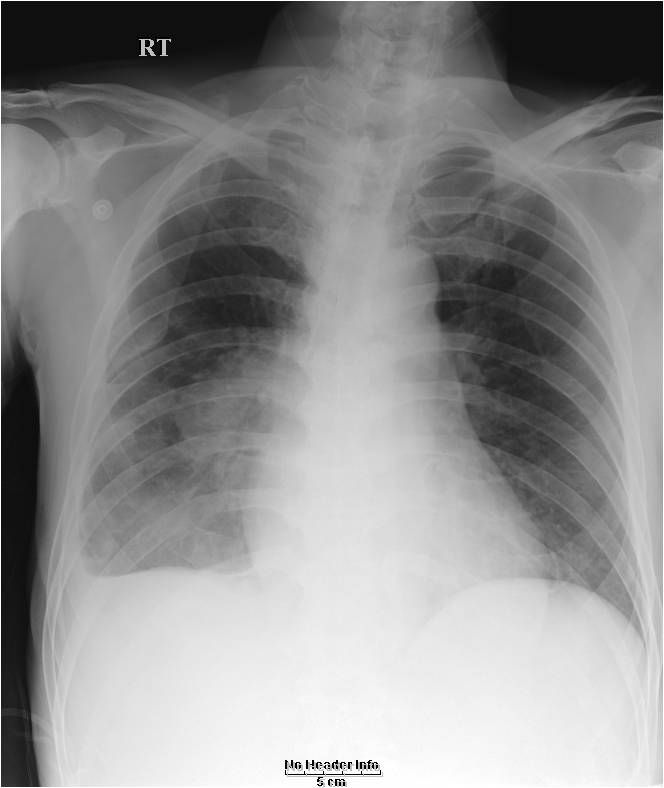

cardiomegaly on x-ray 11/F

Kyungsun Nam, Department of Radiology, Yonsei University College of Medicine

HIT : 16